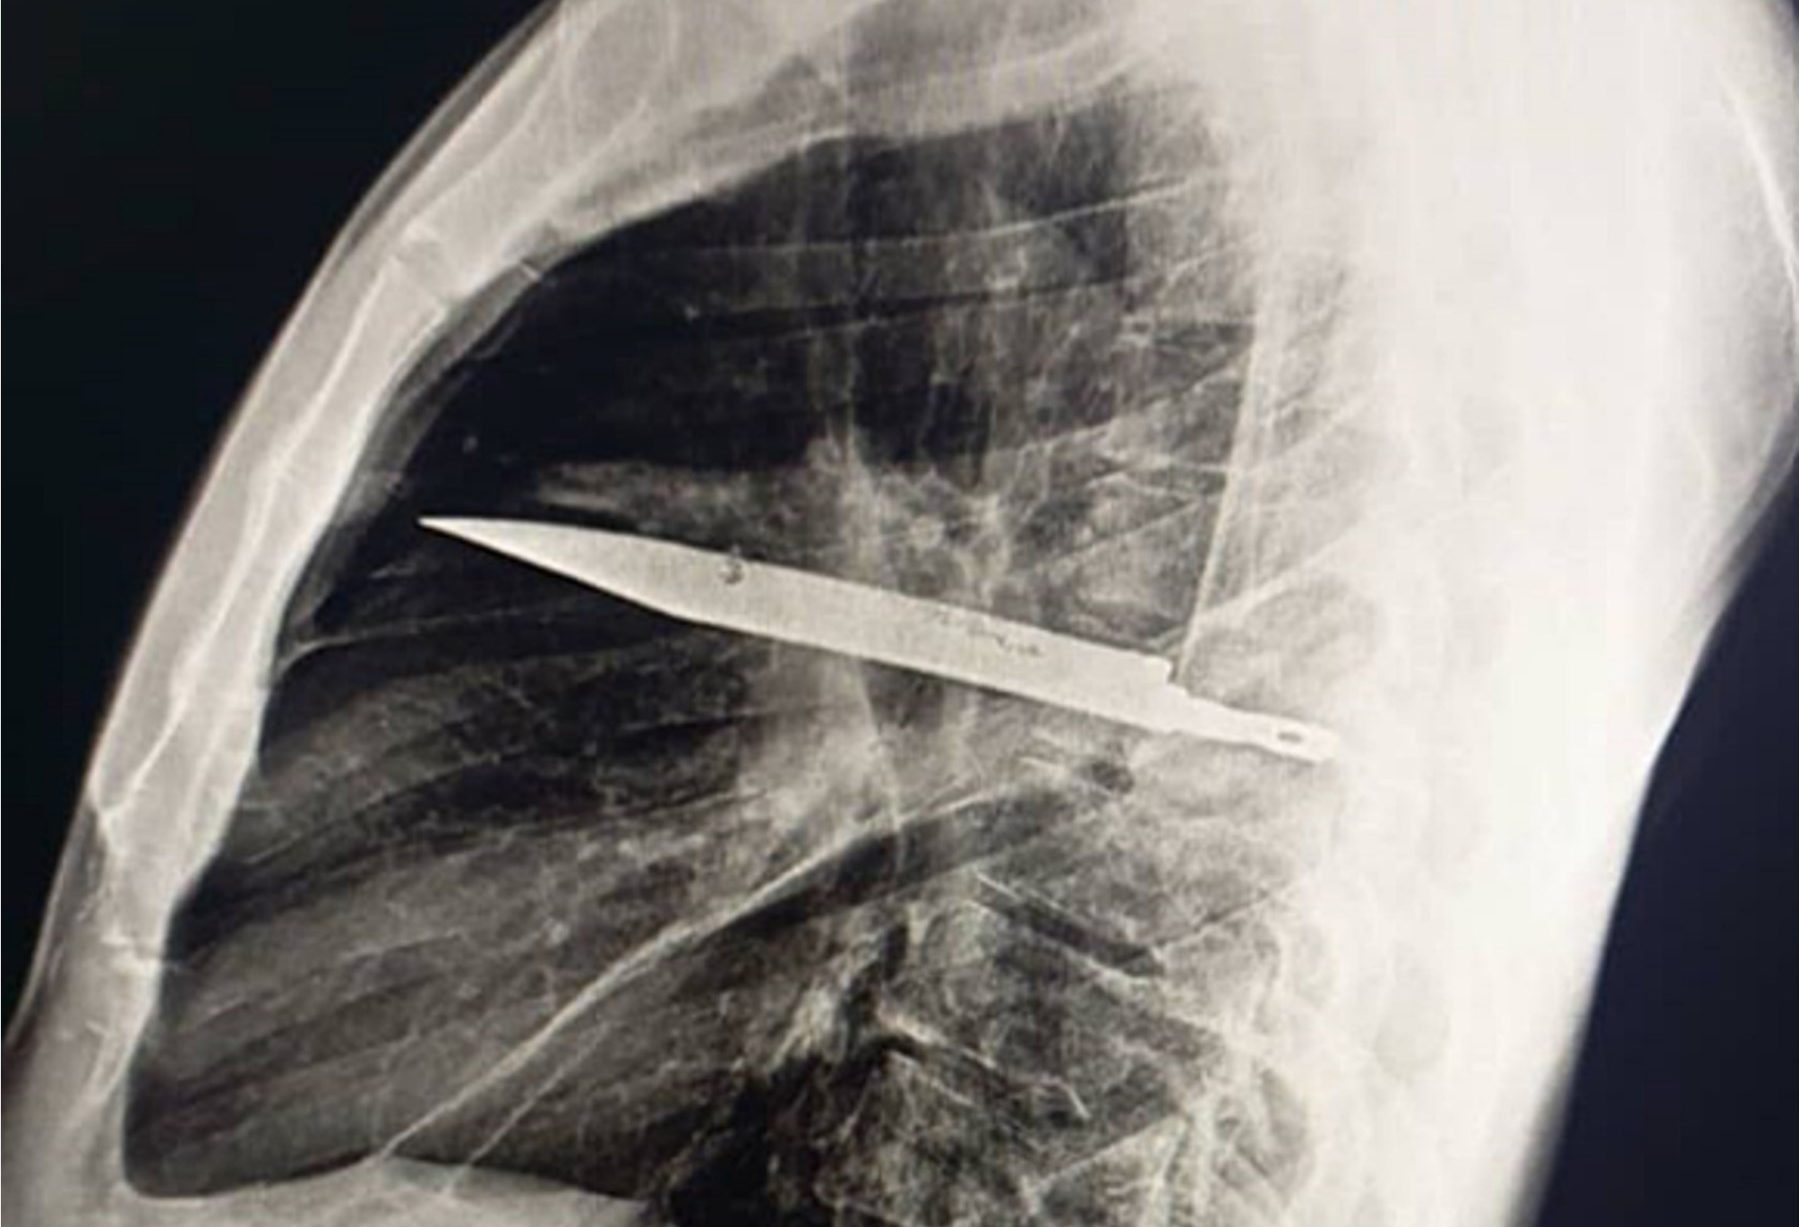

Tout a commencé par un petit écoulement de pus sous son mamelon droit. Ça durait depuis une dizaine de jours. Ce n’était même pas douloureux, il n’avait pas de fièvre, rien d’alarmant en apparence. Les médecins ont d’abord pensé à une simple infection. Mais comme ils ne trouvaient pas la cause, ils ont décidé de faire une radio. Et là, stupéfaction générale. La radio a montré quelque chose de totalement inattendu : une imposante lame de couteau était coincée dans sa cage thoracique. Oui, vous avez bien lu. Une lame, plantée là depuis huit longues années, sans qu’il ne s’en soit jamais rendu compte.

En fait, son système immunitaire a fabriqué une paroi très solide avec une substance naturelle appelée le collagène. Cette coquille a isolé le couteau du reste du corps, empêchant une grosse infection et une inflammation. C’est grâce à ce bouclier naturel qu’il a pu vivre toutes ces années sans rien sentir. C’est fou, non ?